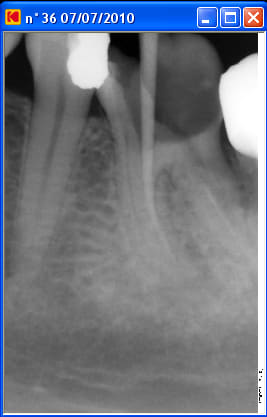

Un patient est venu pour la première fois en urgences pour douleur mandibulaire gauche: bilan radioclarté apicale sous la racine mésiale de 36, test percussion +++, ATB, disparition des douleurs à ce jour.

A la radio il y a une fausse route dans la racine mésiale.